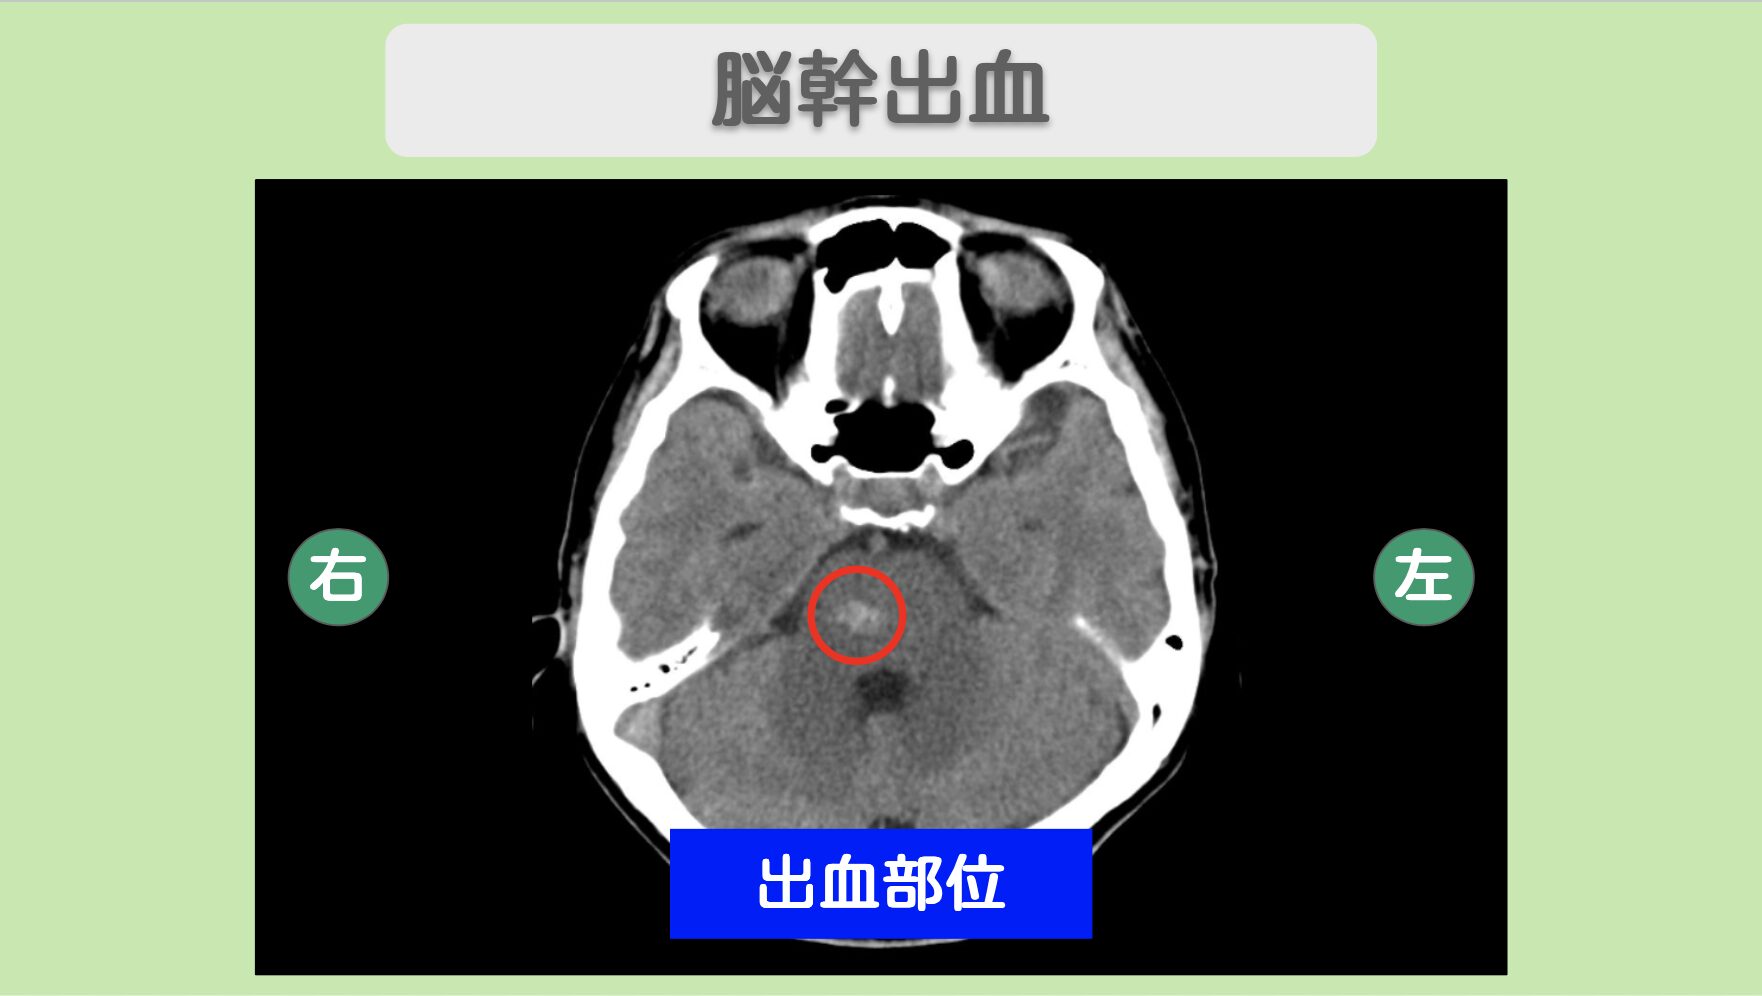

CT所見

脳幹(橋〜中脳付近)に小さな高吸収域(白く映っている部分)が認められます